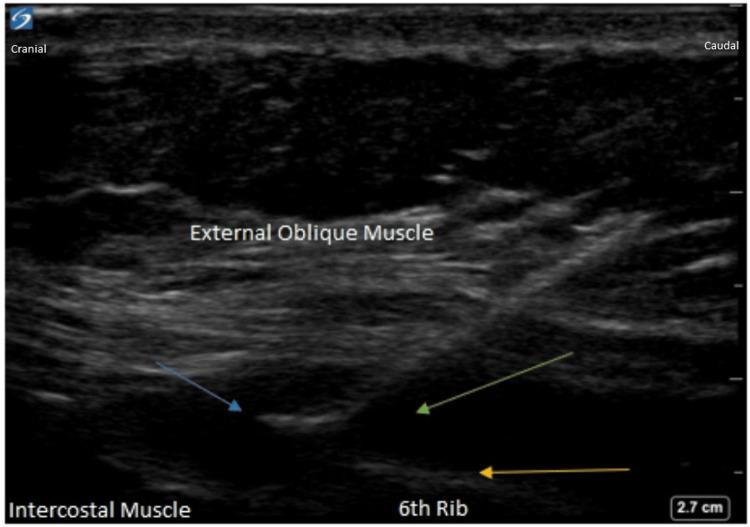

We present the case of a 56-year-old female with a significant medical history of cholelithiasis and recurrent choledocholithiasis. Following an elective cholecystectomy, an obstructing gallstone in the common bile duct led to a series of interventions, including endoscopic retrograde cholangiopancreatography and stent placement. The patient was scheduled for a robot-assisted laparoscopic common bile duct exploration. Due to severe adhesions, the procedure was converted to open with a large right upper quadrant incision. Intraoperative continuous external oblique block and catheter placement were performed at the end of surgery in the OR. Peripheral nerve blocks have become an integral part of multimodal pain management strategies. This case report describes the successful implementation of an ultrasound-guided right external oblique intercostal block and catheter placement for postoperative pain control and minimization of opioids. This case highlights the efficacy and safety of ultrasound-guided peripheral nerve blocks for postoperative pain management. Successful pain control contributed to the patient's overall postoperative recovery.

我们报告一例56岁女性病例,该患者有胆石症和复发性胆总管结石的重要病史。在择期胆囊切除术后,胆总管内的阻塞性胆结石导致了一系列干预措施,包括内镜逆行胰胆管造影术和支架置入。患者计划接受机器人辅助腹腔镜胆总管探查术。由于严重粘连,手术改为经右上腹大切口开放手术。术中在手术室手术结束时进行了持续的腹外斜肌阻滞和导管置入。外周神经阻滞已成为多模式疼痛管理策略的一个组成部分。本病例报告描述了超声引导下右腹外斜肌肋间阻滞和导管置入用于术后疼痛控制及减少阿片类药物使用的成功实施。本病例突出了超声引导外周神经阻滞用于术后疼痛管理的有效性和安全性。成功的疼痛控制有助于患者的术后整体恢复。